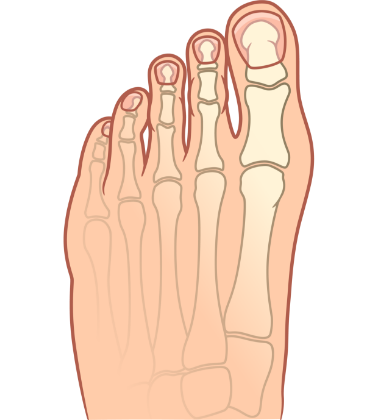

POSLIJE

Prsti su vratili pravilan položaj, a bolne i neestetske deformacije kostiju stopala su nestale.